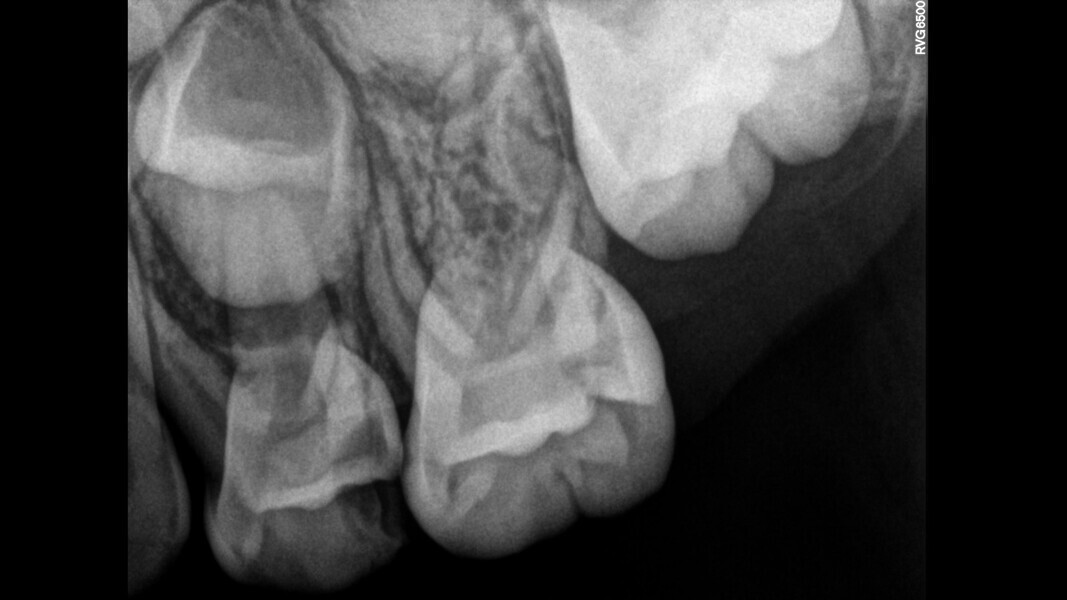

Case 2 (Figs. 5–9)

This male patient was 6 years and 7 months old and presented with severe tooth decay on the mandibular left first primary molar without any symptoms of pain. He experienced slight discomfort to percussion and palpation of the buccal gingiva. A buccal abscess and no mobility were observed. The radiograph showed a large area of interradicular bone loss. The tooth was diagnosed with pulp necrosis and an asymptomatic apical abscess. Pulpectomy was performed, and at a second appointment, a stainless-steel crown was placed upon confirming absence of signs or symptoms of disease. At the 14-month recall, no clinical pathology was detected and a normal eruptive process of the permanent premolars was observed in spite of the extrusion of the obturation material.